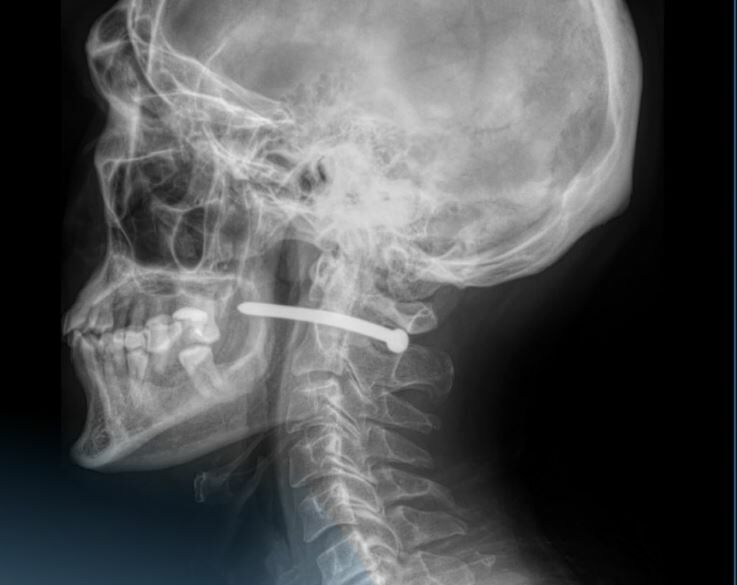

- Гвоздь прошел в непосредственной близости от шейного отдела позвоночника. Мужчине чудом повезло. Жизненно важные структуры не были задеты, - рассказали в пресс-службе многопрофильной городской больницы.

Гвоздь вошел прямо в область за ухом. Хирурги действовали быстро и ювелирно. Они вытащили металлический предмет, провели ревизию раны, наложили швы и стерильную повязку. После этого счастливчика отпустили домой.